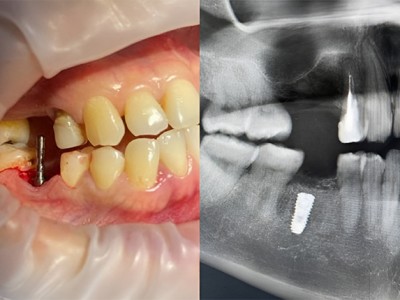

- Истории пациентов - Стоматология